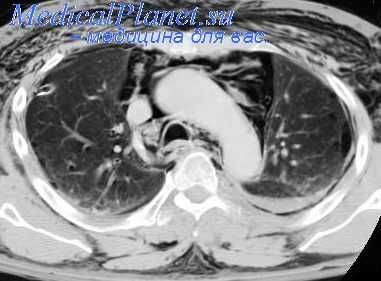

За последние годы при дифференциальной диагностике различных заболеваний средостения с успехом применяют рентгеноэлектрокимографию. Этот метод состоит в записи кривой колебаний движений органов средостения с помощью особого аппарата — электрорентгенокимографа. С помощью фотоэлемента улавливаются изменения освещенности рентгеновского экрана, вызванные колебанием контуров сосудов, сердца, органов.

Образовавшийся поток электронов дает начало электрическому току, который усиливается электронным усилителем и записывается на движущейся ленте бумаги в виде кривой. На рисунке показан электрокимограф, который применяется в нашей клинике В. В. Зарецким. На кривой пульсации хорошо выражены диастолические и систолические зубцы, достигающие высоты 25—30 мм. Установлено, что каждый отдел сердца и крупных сосудов имеет характерную кривую пульсации.

Электрокимография играет большую роль в диагностике пороков сердца и крупных сосудов. Одновременно этот метод может быть использован при дифференциальной диагностике между аневризмами сердца и аорты, а также опухолями и кистами средостения [Гаубрих (Haubrich, 1955); данные нашей клиники].

С помощью электрокимографа можно записать пульсацию исследуемого образования в средостении на любом участке его контура и выяснить характер этой пульсации. При аневризме определяется собственная пульсация контуров тени, а при кисте или опухоли — передаточная. Собственная пульсация аневризмы по характеру напоминает пульсацию той области или того сосуда, из которого эта аневризма исходит.

При аневризме меняется лишь амплитуда колебаний контура, что связано с тромбозом ее просвета или образованием аневризматической чашки. По мере истончения стенки аневризмы пульсация усиливается и, наоборот, затухает после отложения извести в ее стенках. Однако форма кривой собственной пульсации всегда остается постоянной. Следовательно, с помощью электрокимографии удается выявить аневризмы сердца и крупных сосудов, определить их точную локализацию, а также характер изменений, происходящих в их просвете и стенке.

Другой вид имеет передаточная пульсация, которая характерна для опухолей и особенно для кист средостения, прилегающих иногда очень интимно к различным отделам сердца и крупных сосудов. По своему типу эта пульсация также напоминает пульсацию того отдела сердца или крупного сосуда, к которому принадлежит киста или опухоль, что важно знать хирургу.

Однако она в значительной степени снижена и изменена на различных участках контура. Участки кисты или опухоли на противоположной сердцу или сосуду стенке напоминают пульсацию этого отдела сердца, сосуда, тогда как другие части контура тени опухоли не имеют характерных сосудистых или сердечных зубцов. Необходимо отметить, что передаточная пульсация распространяется только в одном направлении.